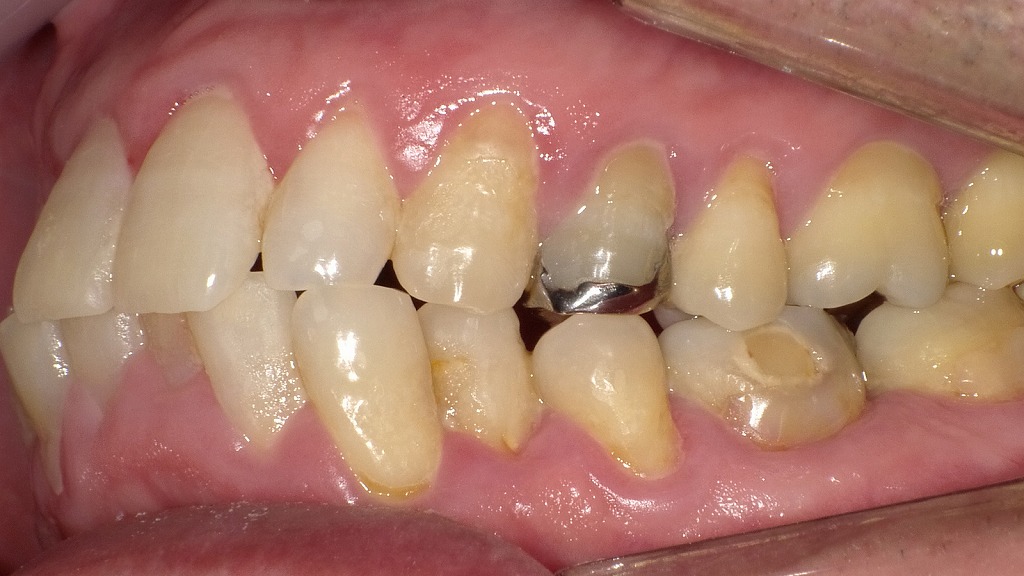

🔸【下顎第一大臼歯に見られる歯肉炎の症例】

🦷【症状1】下顎6番(第一大臼歯)からの出血

- 下顎奥歯(6番)の歯ぐきから出血が確認されています。

- 歯肉炎が大臼歯部に限定的に発症している典型的なケースです。

🦷【症状2】上顎犬歯からも顕著な出血

- 下顎だけでなく、上顎犬歯(3番)からも明らかな出血が認められます。

- 一部の部位にとどまらず、複数の部位に炎症が波及していることが考えられます。

🔍【補足】考えられる原因と必要な対応

継続的なメンテナンスと生活習慣の見直しも重要です。

奥歯や犬歯周囲は歯ブラシが届きにくく、プラークが残りやすい部位です。

正しいブラッシング指導や**歯石除去(スケーリング)**によって症状の改善が見込めます。

🦷【成人の下顎前歯における歯肉炎の術前・術後比較】

🩺【術前の状態】歯肉炎が見られる下顎前歯の症例

- 下顎前歯の歯ぐきがわずかに腫れており、軽度の出血も認められます。

- 特に**歯間乳頭部(歯の間の歯ぐき)**は丸く腫れており、炎症による腫脹の典型的な所見です。

- この段階では、歯垢や歯石の蓄積による慢性的な刺激が原因と考えられます。

🧼【術後の状態】歯肉炎治療後の改善した歯ぐき

- 歯石除去・歯面清掃(PMTC)・歯磨き指導を実施後、歯ぐきの状態が明らかに改善。

- 腫れは引き、出血もなくなり、歯ぐきは健康的なピンク色を取り戻しています。

- 歯肉は引き締まり、仮性ポケットも改善傾向にあります。

- なお、完治にはさらに時間が必要であり、今後も定期的なメンテナンスとセルフケアの継続が重要です。